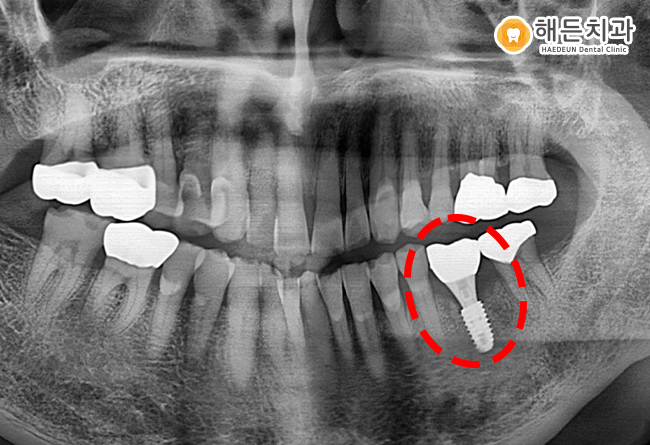

위 사진은 천안아산치과 내원하신 김*렬님의 치아 사진입니다.

김*렬님은 몇 년 전 타치과에서 신경치료 완료 후, 이따금씩 잇몸이 부어 천안아산치과 해든치과에 내원해 주셨습니다.

X-Ray 사진으로 보았을 때 빨간색 점선으로 표시된 하악 왼쪽(사진상으로 오른쪽) 어금니 뿌리 끝을 자세히 보시면

다른 곳과 다르게 검은색으로 빈 공간처럼 생긴 부분이 보이실 겁니다.

해당 부분은 어금니 끝 쪽에 염증이 생겨, 잇몸뼈가 녹아 검게 보이는 것인데요.